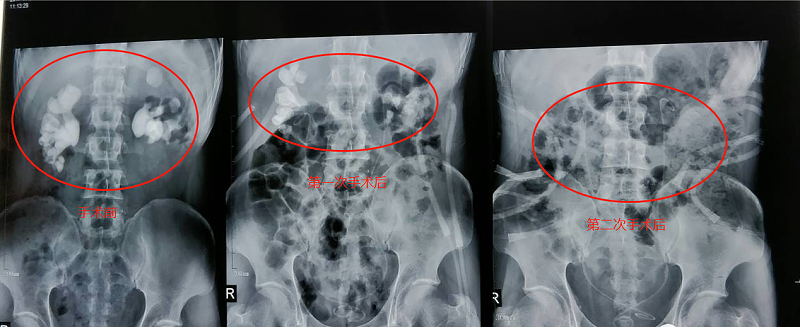

11月8日,雅安仁康醫(yī)院采用上述方案為患者進(jìn)行了雙側(cè)經(jīng)皮腎鏡碎石取石術(shù)。手術(shù)進(jìn)行了兩小時(shí),幾乎沒(méi)有出血,術(shù)后也沒(méi)有出現(xiàn)其他并發(fā)癥。手術(shù)后復(fù)查X線照片顯示,右腎結(jié)石已清除一半,左腎結(jié)石清除70%。在病人身體恢復(fù)后,11月14日病人又進(jìn)行了二次手術(shù),依然采用第一次方案,采用雙側(cè)同時(shí)經(jīng)皮腎鏡碎石取石。術(shù)后復(fù)查X線照片顯示雙腎“巨無(wú)霸”結(jié)石已消失。目前,洛大叔腎功能已恢復(fù)正常,身體情況也恢復(fù)良好,沒(méi)有出現(xiàn)術(shù)后并發(fā)癥,準(zhǔn)備近期出院。

腎結(jié)石對(duì)比

檢查照片對(duì)比圖